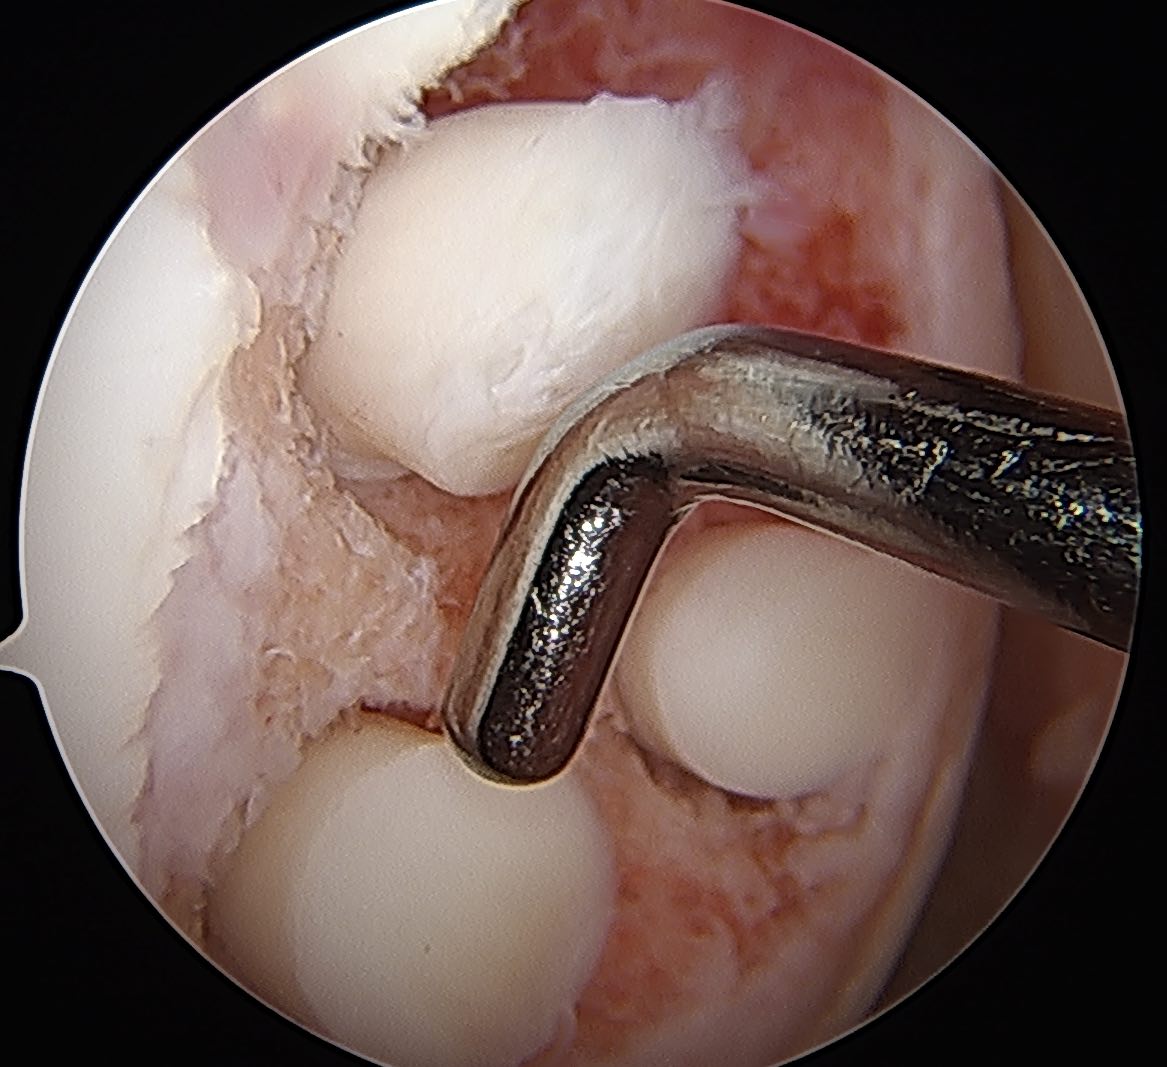

Arthroscopic Screw Fixation in situ

Arthroscopic bone graft and screw fixation

MFC unstable OCD

LFC unstable OCD